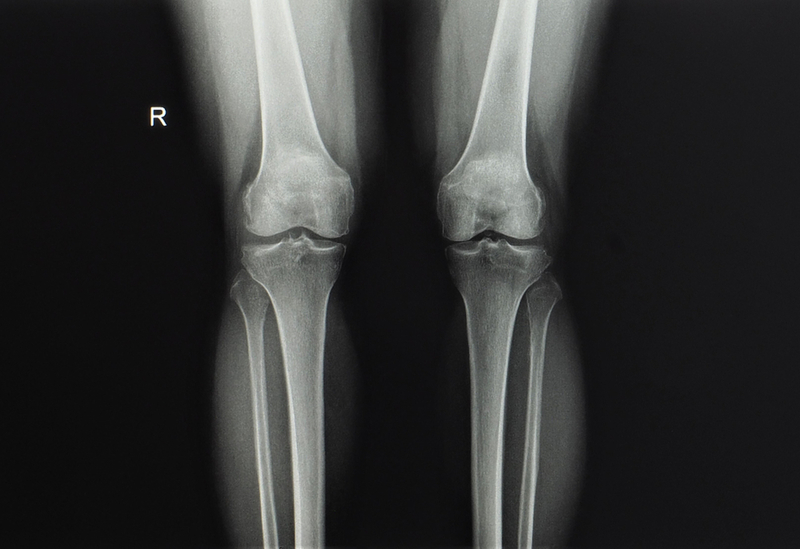

Addressing the conference organised by Udai Omani Hospital to create awareness on Osteotomy,on June 2, surgeons said that most of the young and middle aged women and men with bowlegs or knock knees opt for knee replacement at an early stage of their lives which would not have longevity beyond 10 or 15 years.

Orthopedic surgeons approved Osteotomy as the best suited alternative to knee replacement to regain an active lifestyle. However, under Osteotomy, the joint is preserved and patients can even get back to active sports and or heavy work, the surgeons claimed. Known as 'cutting of a bone', Osteotomy is a surgical technique used to correct deformities by realigning the bones of the leg to ensure the pressure on the damaged joint is relieved, the surgeons said.

The bone (either the femur or the tibia) is cut, the alignment is corrected, the gap is filled with a bone and supported by metal plate, and this process is often seen as once in a lifetime solution for their problems, the Orthopaedic Surgeons said. This procedure can also be done in teenagers and young people who have deformities around their knees, they said this ensures that these youngsters do not develop arthritis at a young age.